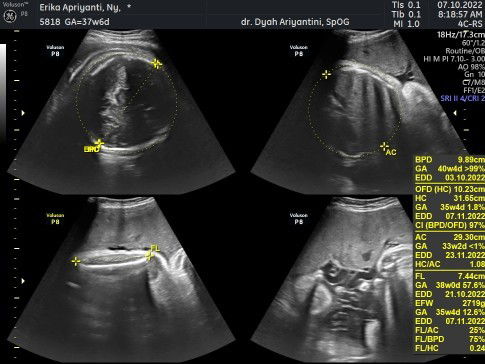

Bun sharing dong klau ada yg pernah ngalamin atau ada yg tahu ,bulan kmarin USG di usia 32week smua normal dan di bulan ini di tgl yg sama harusnya kan usia 36week tp kok kata dokternya 38week sedangkan klo mnurut hpht baru 37 week bun . tp dari hasil USG kok perbedaan nya jauh bgt ya Bun ada yg udah 40week ada yg msih 33week.. jadi kepikiran Bun .sedangkan dokternya ga bilang apa" ga ngejelasin apa" dan BBJ masih 2,7 bun.mnurut bunda" gimana ya?? soalnya jadi bingung aq tanya ke dokter katanya gpp , pertama kali ganti dokter SpOG tp hasilnya beda dan penjelasan nya masih kurang buat saya jadi kepikiran bun ,#seriusnanya #bantusharing #firstmom